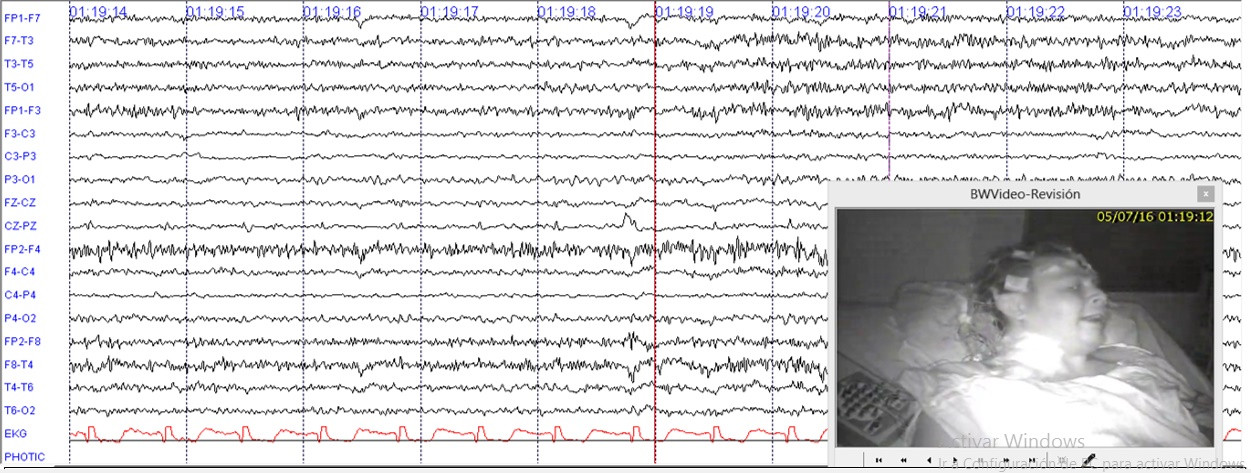

Because the individual was presenting faciobrachia dystonic seizure, hence the presence of a potassium channel, mediated autoimmune epilepsy was considered. Infectious and neoplastic diseases were ruled out. Cranial MRI was normal. An EEG for twelve hours (Figure 1) was done and showed multiple episodes of faciobrachia dystonic seizure per hour accompanied by rapid path attenuation, more widespread activity during and after the episodes.

Figure 1 12 hours of EEG with LFF at 1Hz and HFF at 70Hz. Illustrates continuous fast activity mixed with muscle artefact during and after faciobrachial dystonic seizure.

Electroencephalographic studies could present with three important variants: (1) interictal findings, (2) ictal findings, (3) focal slowing. But in our case, we found attenuation and generalized fast activity during and after episodes of faciobrachial seizure in VGKC patient and continuous slow complex in NMDA-R antibodies patient. There was no clear ictal or interictal findings. Most commonly, CSF can be documented with inflammatory changes by up to 31%; hyperproteinorrachia, 55%; oligoclonal bands, 19%; leucorrachia, 16%; or finally, normal 38% as in the case of our two patients.